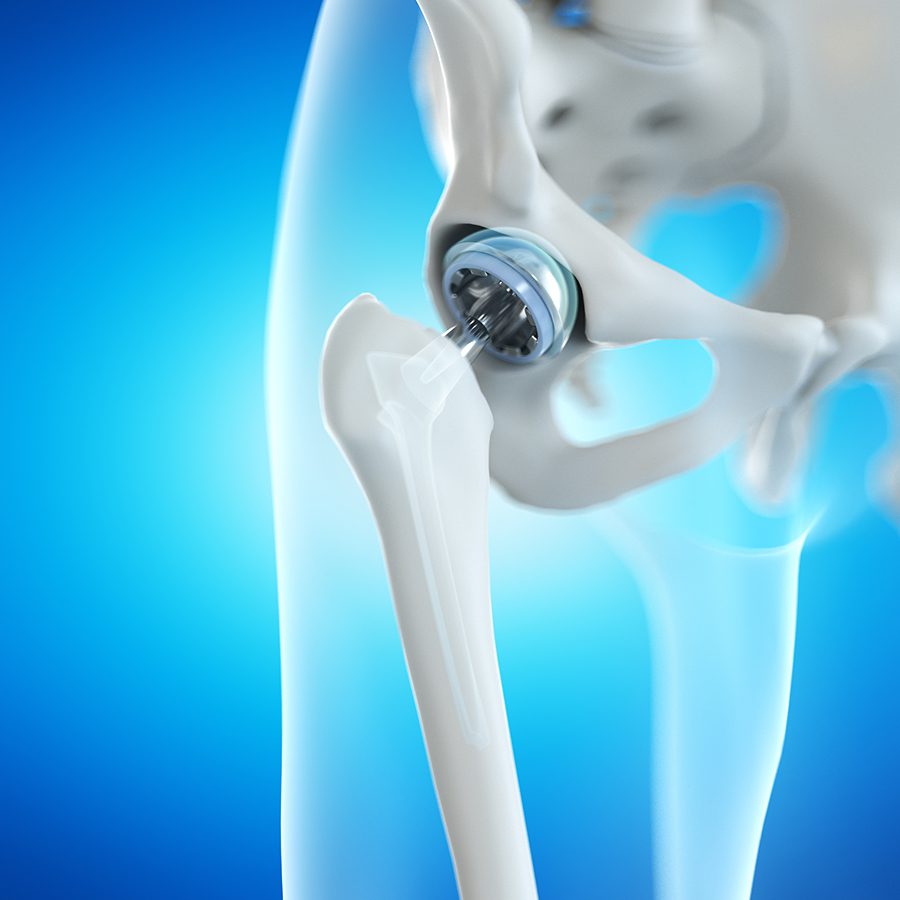

What Is Hip Joint Replacement

What Is Hip Joint Replacement

Direct Superior Hip Replacement Overview

Total Hip Replacement BJISG

Total Hip Replacement Hip Osteoarthritis